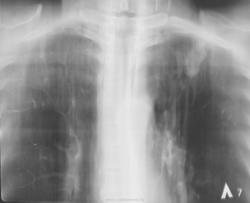

В облтубе пациента решили прооперировать.

Да, после удаления, верификация - туберкулома.